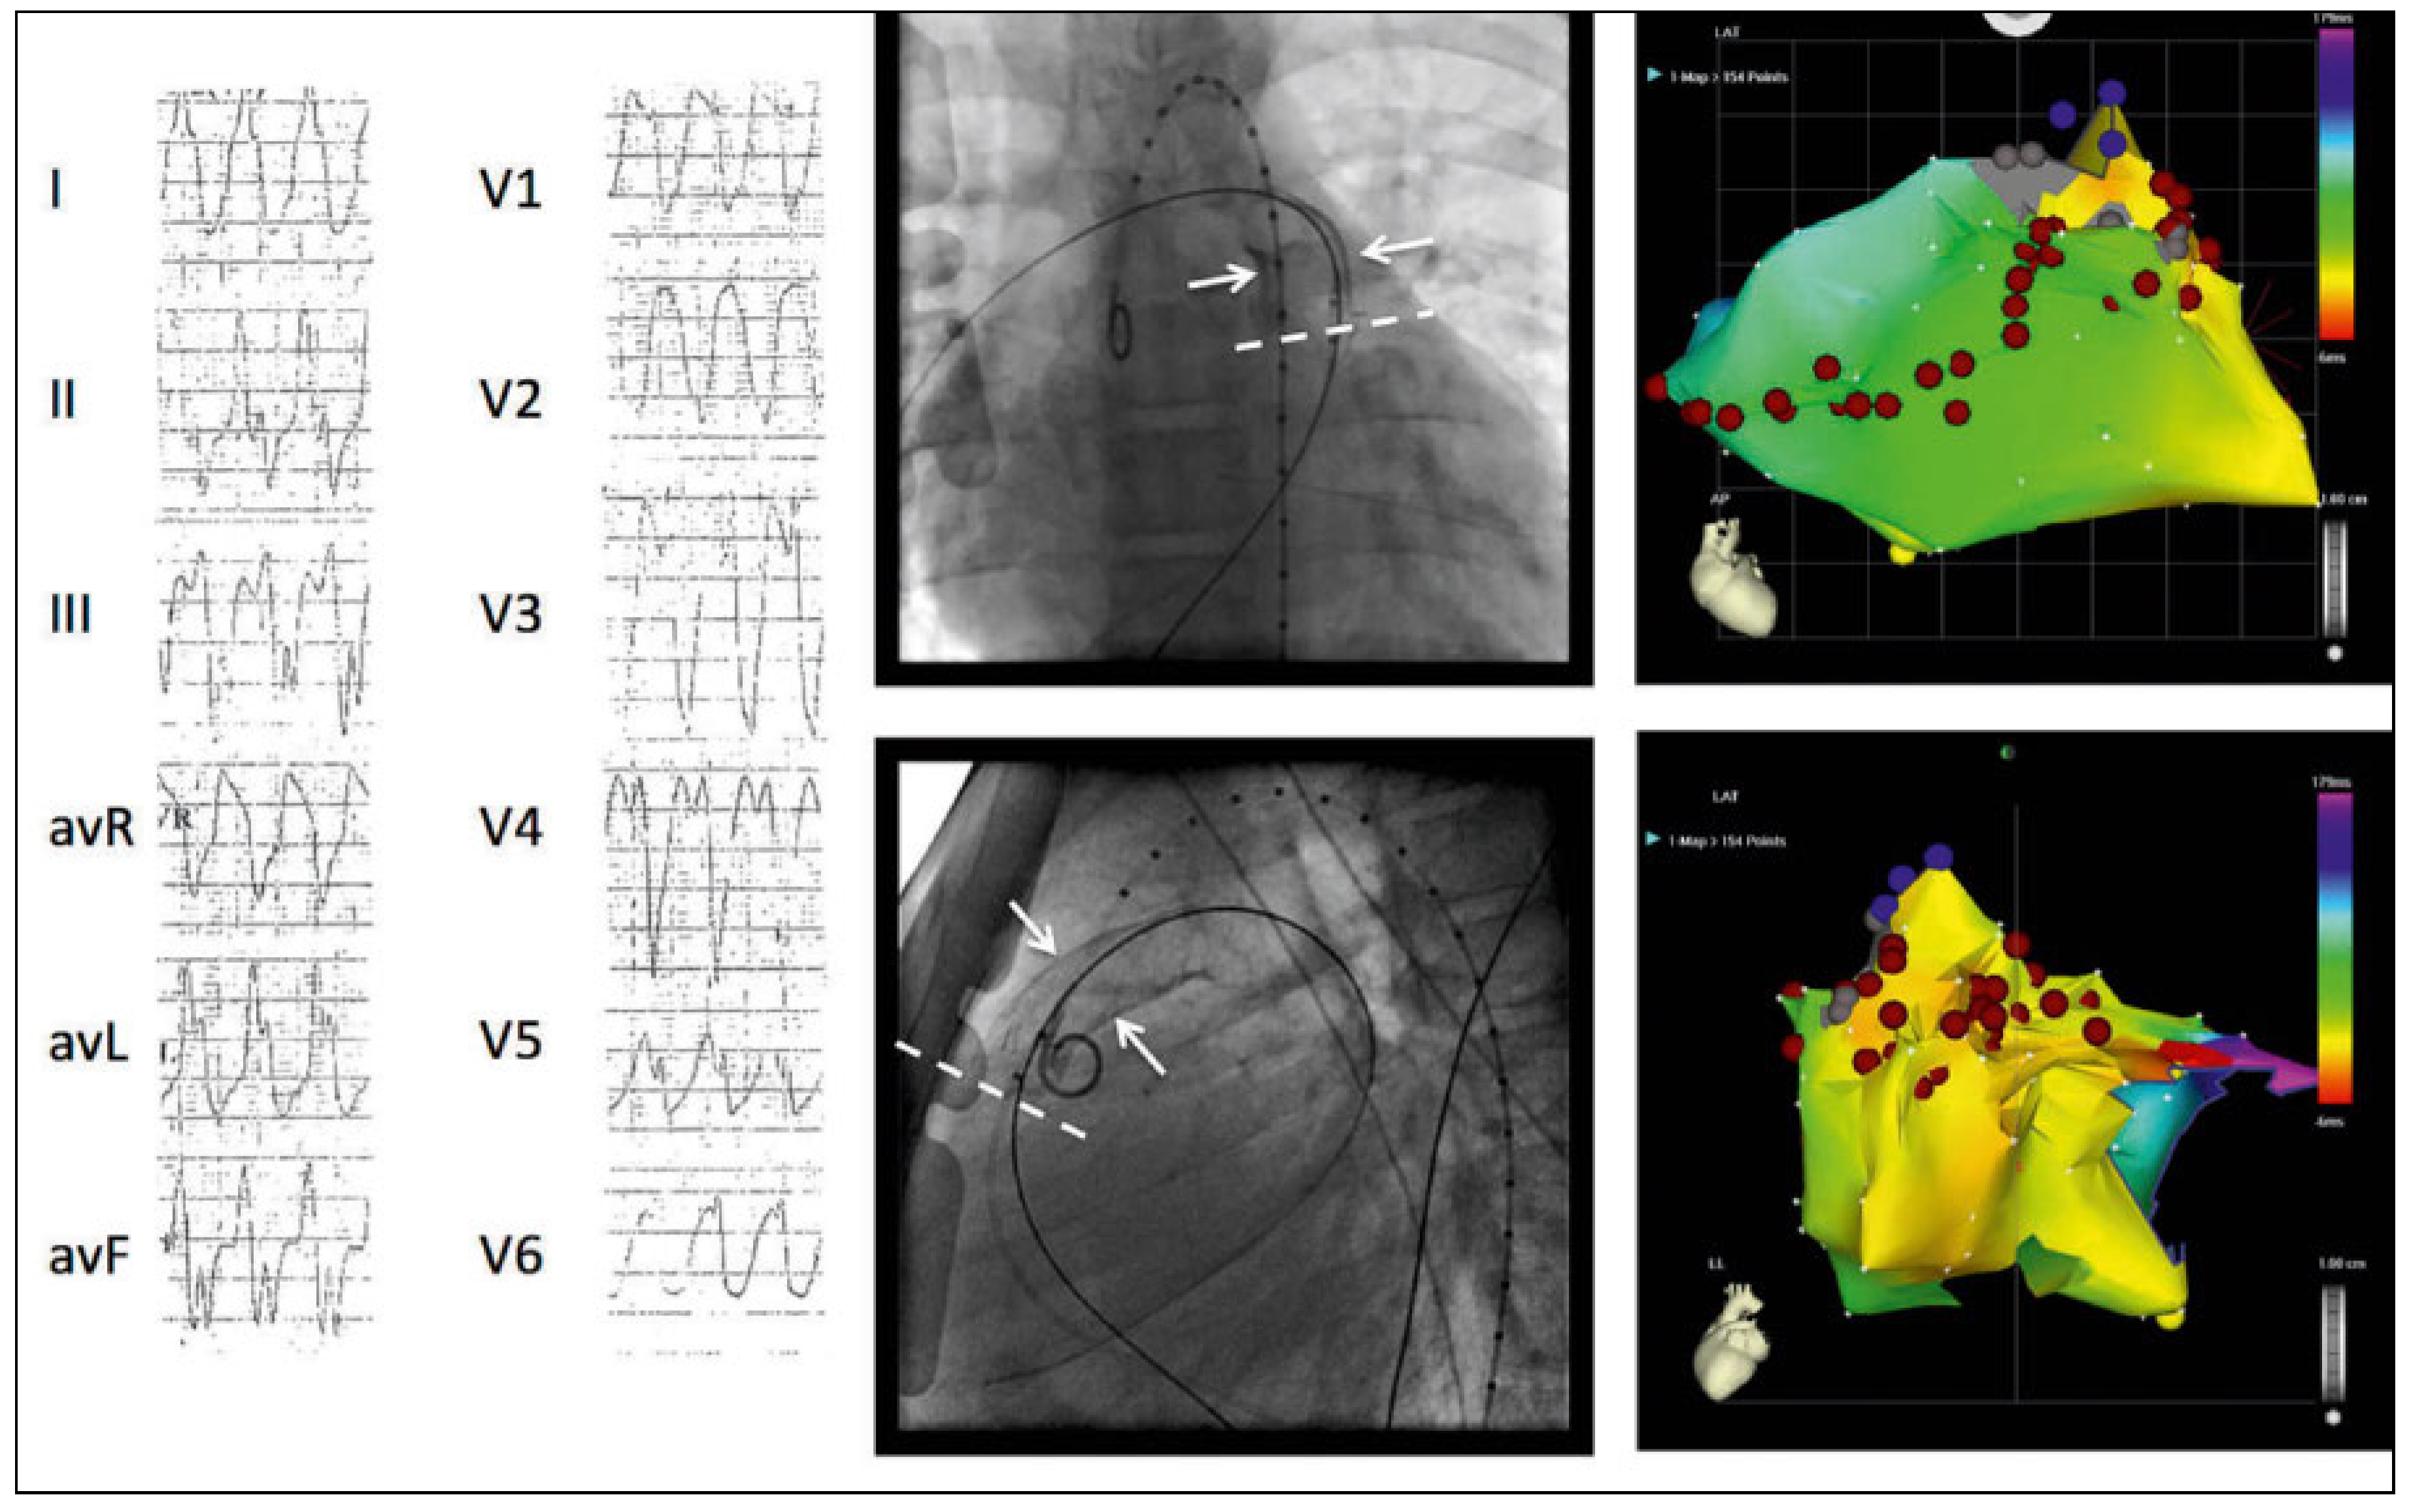

Figure 2. Left panel shows the ECG of the second VT (VT2), induced after creating the right ventricular (RV) free wall linear lesion, with a morphology indicating a septal superior exit (QR in V1, transition V3). Middle panel shows a recording during this VT at the septal junction of the RV summit with the conduit (white arrow in right panel). Recording shows, from top, leads II, III, V1 and V6 and from the ablation catheter placed at the septal RV summit showing prominent diastolic fractionated potentials (DP), larger in amplitude and sharper in the proximal electrodes of the ablation catheter (Abl p). Also shown are RV electrograms (VD1–4) with a clearly systolic timing. Right panel shows an electro-anatomic sinus rhythm voltage map with purple indicating bipolar endocardial voltage greater than 1.5 mV and all other colours a lower voltage, clearly centered around the base of the conduit and in the septal superior and peritricuspid region including the area where DPs were recorded during VT2.

The clinical VT demonstrated a left bundle-branch block and leftward axis configuration with a precordial transition indicating a right ventricular free wall exit. A sequence of contiguous radiofrequency lesions was created on the anterior wall of the right ventricle extending from the inferior border of the anterior zone, and continuing to the anterior border of the tricuspid annulus (Figure 1, left and right panels). Additional lesions were made in the narrow zone of normal-voltage tissue interposed between the septal and anterior scar zones. Inducibility testing confirmed that the clinical VT could not be induced, but a different sustained monomorphic VT was induced (VT2), with an inferior axis, QR morphology in V1 and a transition in V3, suggesting a septal superior exit, probably nearer the septal left ventricular outflow tract patch (figs 1 and 2, right panels). Diastolic potentials were recorded on the right ventricular side of this region during on-going VT (Figure 2, centre panel), and because of proximity to the His bundle potential, radiofrequency lesions were prudently delivered to this region in sinus rhythm (Figure 3). Although a VT similar in morphology to the second VT remained inducible thereafter, no further attempts at ablation in this region or on its corresponding left side were made in view of the proximity to the atrioventricular conduction system and noninducibility of the clinical VT. A couple of weeks later, the conduit was surgically revised for haemodynamically significant stenosis and a single chamber ICD implanted without complications or arrhythmia recurrence. Over 5 years of follow-up, although he had an ICD intervention during early follow-up (unclear whether appropriate), he has been doing well for the last 3 years without antiarrhythmic therapy and without any further ICD intervention.